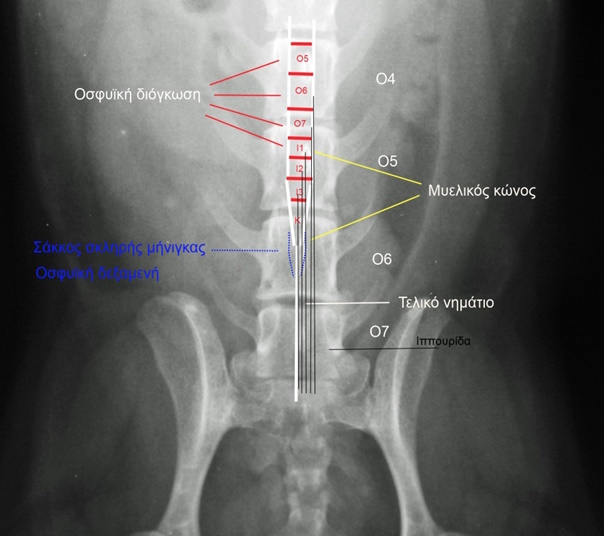

Το τελευταίο τμήμα του ΝΜ ονομάζεται μυελικός κώνος. Στους περισσότερους σκύλους ο μυελικός κώνος εντοπίζεται πίσω από την οσφυοϊερή διόγκωση. Η οσφυοϊερή διόγκωση είναι το τμήμα του ΝΜ από όπου ξεκινούν τα νεύρα που νευρώνουν τα οπίσθια άκρα και την πυελική κοιλότητα. Η οσφυοϊερή διόγκωση περιλαμβάνει τμήμα του νευροτομίου Ο5, το νευροτόμιο Ο6, το νευροτόμιο Ο7 και τμήμα του νευροτομίου Ι1. Ανατομικά εκτείνεται κατά μήκος των σπονδύλων Ο4 και Ο5 (στη γάτα Ο5 και Ο6).

Ο μυελικός κώνος περιέχει τα νευροτόμια I2, I3 και Κ (1-5). Τα νευροτόμια αυτά είναι μικρά και περιβάλλονται από ρίζες νωτιαίων νεύρων που έχουν πορεία προς τα πίσω. Ανατομικά τα νευροτόμια του μυελικού κώνου περιέχονται στο οπίσθιο ήμισυ του σπονδύλου Ο5 ή στο πρόσθιο ήμισυ του σπονδύλου Ο6. Στις μικρόσωμες φυλές ο μυελικός κώνος εντοπίζεται οπισθίως του σπονδύλου Ο6.

Περίπου 1cm πίσω από το τελευταίο νευροτόμιο η περιοχή της οσφυοϊερής μοίρας του σπονδυλικού σωλήνα ονομάζεται ιππουρίδα. Η ιππουρίδα συνίσταται από τις ρίζες του νεύρου Ο7, των ιερών (Ι1-Ι3) και των κοκκυγικών (ΚΙ-Κ5) νεύρων που φέρονται προς τα πίσω παράλληλα με το τελικό νημάτιο που το καλύπτουν όπως οι τρίχες την ουρά του ίππου.

Κοιλιοραχιαία ακτινογραφία της οσφυοϊερής μοίρας που απεικονίζεται η οσφυϊκή διόγκωση και τα νεύρα της ιππουρίδας

Δύο cm πίσω από το τέλος του ΝΜ και πριν η σκληρά μήνιγγα αρχίσει να περιβάλλει το τελικό νημάτιο, υπάρχει ο σάκος της σκληρής μήνιγγας (dural sac). Στο σημείο αυτό υπάρχει υπαραχνοειδής χώρος με ΕΝΥ που ονομάζεται οσφυϊκή δεξαμενή.

Εντός του σπονδυλικού σωλήνα και πίσω από τον μυελικό κώνο η περιοχή ονομάζεται ιππουρίδα (δέσμη νεύρων). Οι ρίζες των νεύρων που συγκροτούν την ιππουρίδα βρίσκονται στον σπονδυλικό σωλήνα που συνιστούν οι σπόνδυλοι Ο5, Ο6, Ο7 και οι κοκκυγικοί.